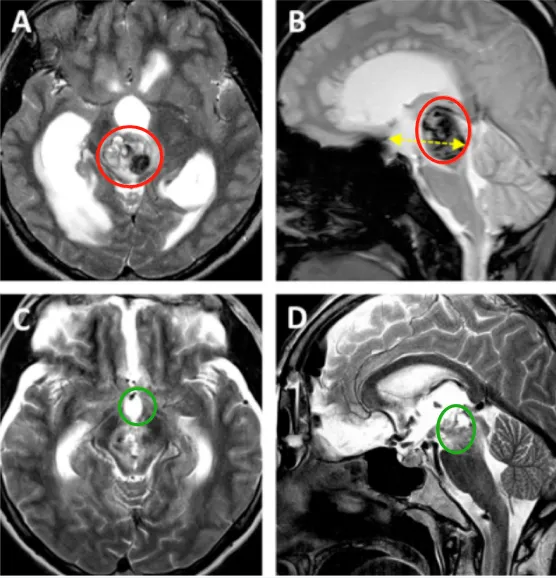

肿瘤位置深在丘脑区域,构成第一重挑战。丘脑作为大脑的信号...

8岁男性患儿小航确诊右侧丘脑-基底节区巨大肿瘤。肿瘤位置深在...